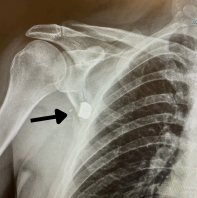

One of the most common concerns people have after they have been shot is whether or not the bullet is still there or not. When a bullet, or a large fragment, larger than a 1⁄4 inch, is left inside your body, we call that a “Retained Bullet” or “Retained Bullet Fragment.” It is not uncommon for bullets to be left inside someone’s body if they do not NEED an operation for a life-threatening reason, such as severe bleeding or a broken bone. And, more than 50% of people are sent home from the hospital after being shot without being admitted at all. This means most people will still have a bullet left in their body if the bullet slowed down and stopped moving inside their body.

Levels of Retained Bullets

When a bullet pierces our skin, the layers of tissue slow it down. Sometimes it is moving fast enough and with enough energy that it will go straight through, but many times the bullet, or a piece of the bullet, will stop. This can happen right under the skin, in the fat layer, in the muscle, in the bone, and in our internal organs. We give each one of those levels a number.

When bullets are level 3, 4 and 5, they are more difficult to remove. You may be advised that the risk of taking the bullet out is worse than what will happen if the bullet stays inside you.

Knowing what level your bullet is can help you plan how to manage it.